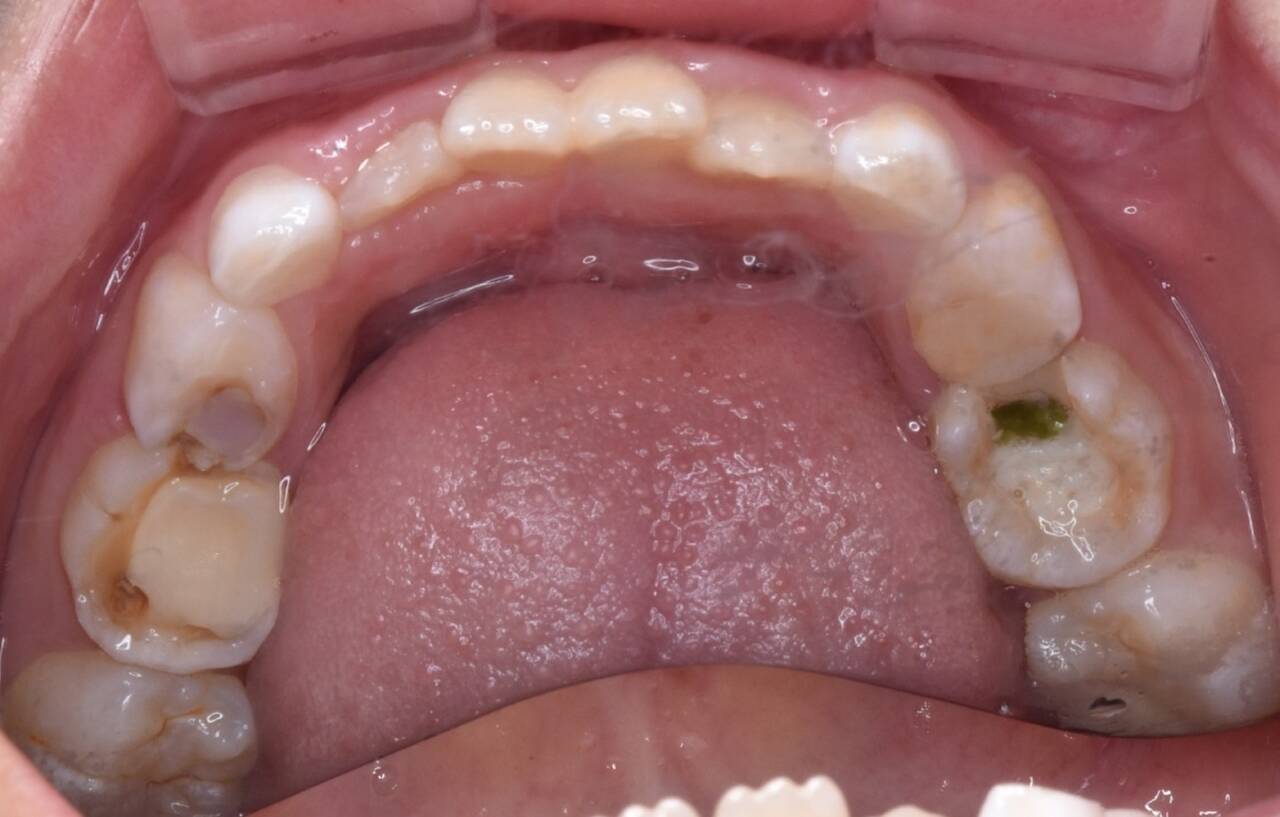

第一次の感染の窓の時期を過ぎても、第二次の感染の窓の時期と呼ばれる時期があります。それが乳歯から永久歯に生え変わる6~12歳です。

この時期は、お口の中の環境に大きな変化が起こり、むし歯菌に感染し、むし歯になりやすくなります。歯磨きが自分磨きになることや、おやつやジュースを摂取する頻度が高まることも影響します。

大人の歯が生えそろった時に、むし歯を経験した歯がゼロなのか、それともむし歯の治療の跡だらけなのかは、今後の人生の健康に影響してくるものです。